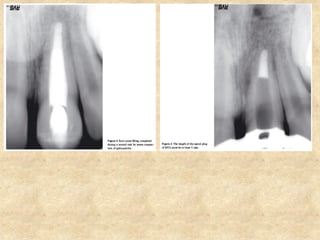

5. Apical plug (Apexification of non vital of immature roots):

• Conventional management of an immature non vital permanent tooth

is apexification with calcium hydroxide.

• The purpose of apexification is to obtain an apical barrier so as to

prevent the extrusion of the obturating material.

• But the disadvantage of using calcium hydroxide is the extended time

taken for the completion of the procedure which may range anywhere

between 3 to 54 months.

• The tooth with calcium hydroxide placed for more than 100 days

showed a significant reduction in fracture resistance.

• This problem is solved with the use of MTA. An MTA plug of 4mm

thickness placed at the apical region is adequate to form a barrier,

sealing the canal from the periapical area.

• Access opening is done under local anesthesia and rubber dam.

• The root canal is cleaned with intracanal irrigants.

• Calcium hydroxide paste can be placed in the canal to disinfect for

about 1 week.

• Calcium hydroxide is removed by rinsing. Excess moisture is removed

from the canal.

• Mixed MTA is placed in the cavity using a large amalgam carrier. The

material is pushed towards the apical foramen with a plugger or paper

points.

• The apical plug should be at least mm thick and this should be checked

radiographically.

• If the apical plug could not be placed adequately, the entire material is

rinsed from the canal with sterile water and the procedure repeated.

• A moist cotton pellet is placed in the canal and the tooth is temporarily

restored.

• After 3 hours, the remaining canal is obturated with gutta percha and a

permanent restoration is then placed.

Steps involved in apical plug placement

5. Apical plug(Apexification of non vital of immature roots): • Conventional management of an immature non vital permanent tooth is apexification with calcium hydroxide. • The purpose of apexification is to obtain an apical barrier so as to prevent the extrusion of the obturating material. • But the disadvantage of using calcium hydroxide is the extended time taken for the completion of the procedure which may range anywhere between 3 to 54 months. • The tooth with calcium hydroxide placed for more than 100 days showed a significant reduction in fracture resistance. • This problem is solved with the use of MTA. An MTA plug of 4mm thickness placed at the apical region is adequate to form a barrier, sealing the canal from the periapical area.

• 30.

• Access openingis done under local anesthesia and rubber dam. • The root canal is cleaned with intracanal irrigants. • Calcium hydroxide paste can be placed in the canal to disinfect for about 1 week. • Calcium hydroxide is removed by rinsing. Excess moisture is removed from the canal. • Mixed MTA is placed in the cavity using a large amalgam carrier. The material is pushed towards the apical foramen with a plugger or paper points. • The apical plug should be at least mm thick and this should be checked radiographically. • If the apical plug could not be placed adequately, the entire material is rinsed from the canal with sterile water and the procedure repeated. • A moist cotton pellet is placed in the canal and the tooth is temporarily restored. • After 3 hours, the remaining canal is obturated with gutta percha and a permanent restoration is then placed. Steps involved in apical plug placement